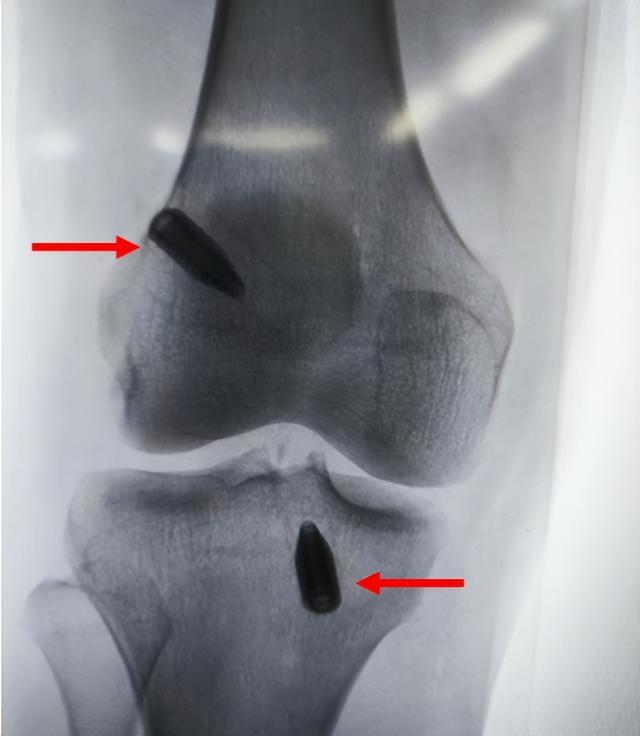

(人工韧带重建)

术后,患者感觉良好,第2天关节屈伸良好,下床活动,第3天顺利出院,家中康复。术后6周复查,患者伤口愈合好,膝关节稳定性恢复正常,屈伸活动完全正常,已恢复日常训练。

(术后X线:内固定稳定)